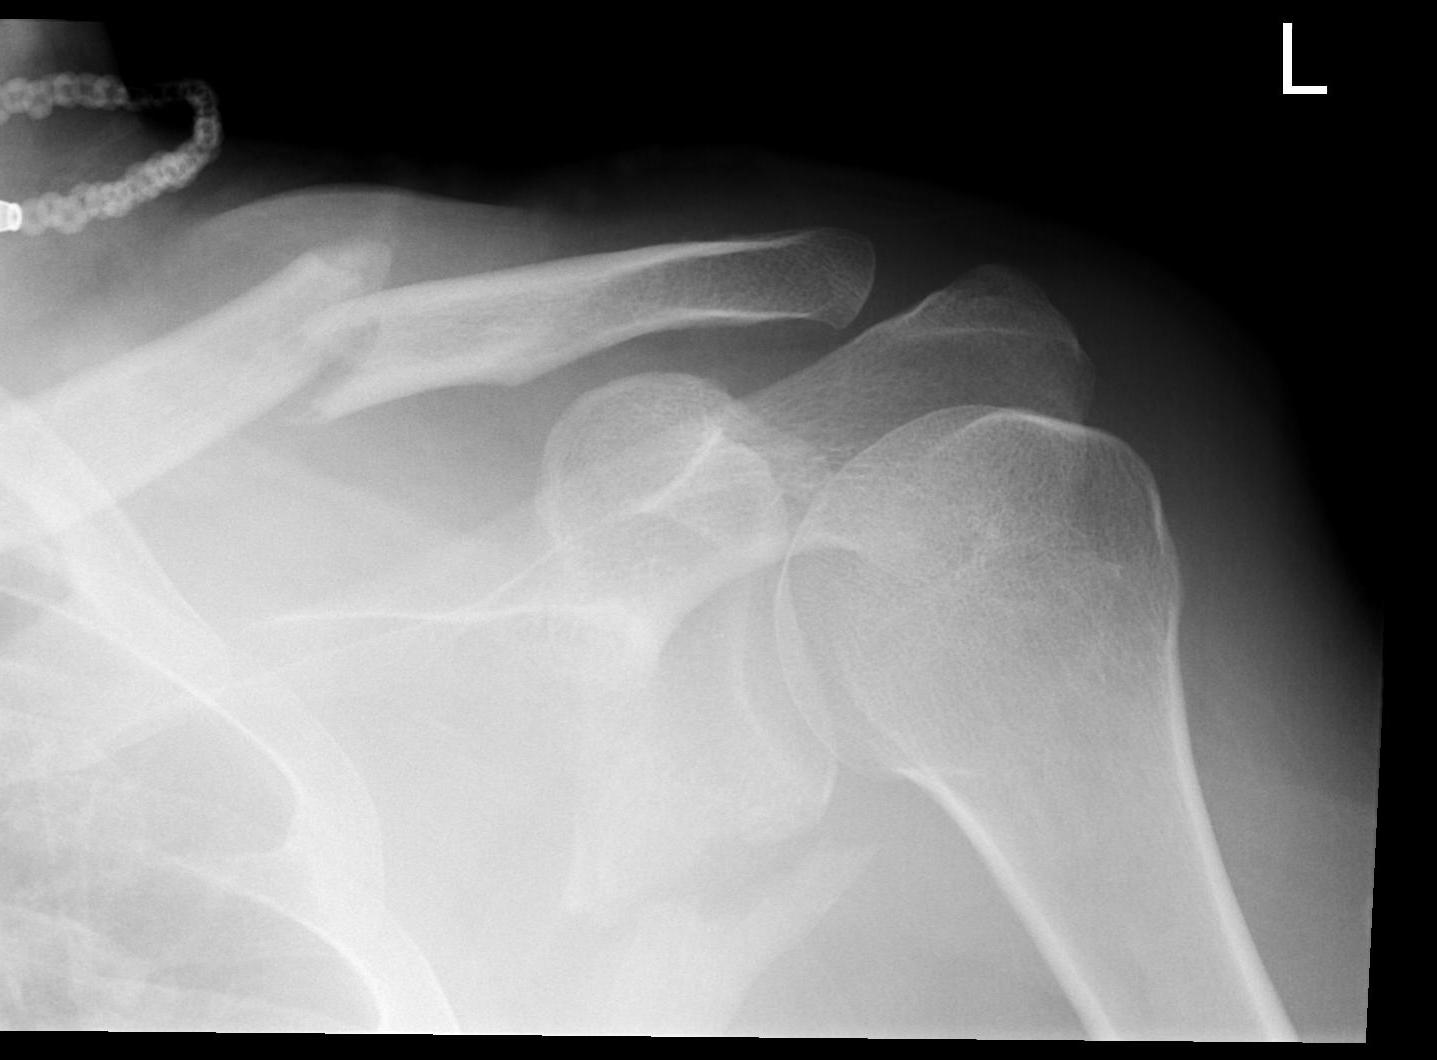

Glenoid fracture + lateral clavicle fracture + acromial fracture

Floatfloatfloat